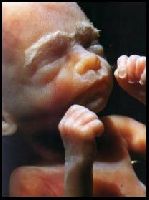

Длина от темени до крестца - около 21 см. Вес - около 530 г.

На этом этапе плод стал крупнее и полнее. Теперь он занимает всю матку, поэтому ему становится тесно. Малыш уже больше не может переворачиваться и кувыркаться в околоплодных водах, но по-прежнему хватается за пуповину и ощупывает все окружающее руками. Сейчас ваше чадо все больше и больше прислушивается к внешнему миру. Если вы испытали испуг, ребенок тоже испугается. Исследования показали, что плод способен оставаться в состоянии возбуждения до нескольких часов, чередуя периоды беспокойства и тревожного замирания. Плод продолжает запасать бурую жировую ткань под кожей. Бурый жир обладает высокой энергетической ценностью, так как при его сгорании в организме образуется большое количество тепла. Новорожденные дети очень плохо удерживают постоянную температуру тела. В результате они очень чувствительны к переохлаждению, которое для них очень опасно. Вот почему ваш малыш так активно занят накоплением бурого жира.

На этом этапе плод стал крупнее и полнее. Теперь он занимает всю матку, поэтому ему становится тесно. Малыш уже больше не может переворачиваться и кувыркаться в околоплодных водах, но по-прежнему хватается за пуповину и ощупывает все окружающее руками. Сейчас ваше чадо все больше и больше прислушивается к внешнему миру. Если вы испытали испуг, ребенок тоже испугается. Исследования показали, что плод способен оставаться в состоянии возбуждения до нескольких часов, чередуя периоды беспокойства и тревожного замирания. Плод продолжает запасать бурую жировую ткань под кожей. Бурый жир обладает высокой энергетической ценностью, так как при его сгорании в организме образуется большое количество тепла. Новорожденные дети очень плохо удерживают постоянную температуру тела. В результате они очень чувствительны к переохлаждению, которое для них очень опасно. Вот почему ваш малыш так активно занят накоплением бурого жира.

Активно развивается дыхательная система плода. Теперь на концах капилляров образовались терминальные мешочки, отделенные тончайшей пленкой от наполненных воздухом альвеол. До этого кислород из легких не попадал в кровеносную систему. А сейчас стало вырабатываться поверхностно-активное вещество сурфактант. Его производство стремительно возрастает на последних неделях. Сурфактант образует тонкую пленку на стенках капиллярных мешочков, отчего они не смыкаются под воздействием дыхания. Данная неделя – начало жизнеспособности ребенка, то есть его способность жить самостоятельно.

У плода появляется собственный ритм сна и бодрствования. Вы почувствуете это, так как сильные толчки будут чередоваться со спокойными периодами. Такой же ритм может сохраниться у него после рождения. Сейчас можно понаблюдать, а потом сравнить, в какое время суток будет спать родившийся малыш. Ребёнок слышит вашу речь, а биение его сердца уже хорошо прослушивается обычным стетоскопом.